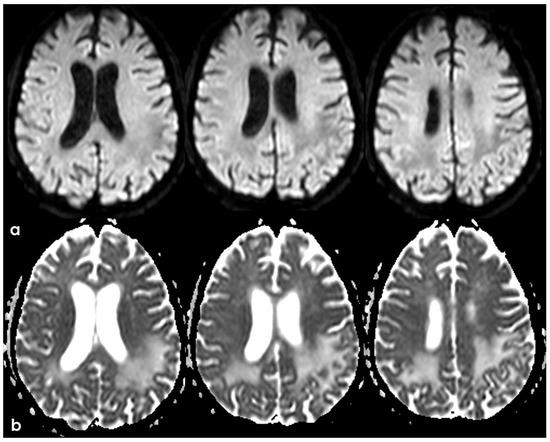

4. December 2015: Ischemic Stroke